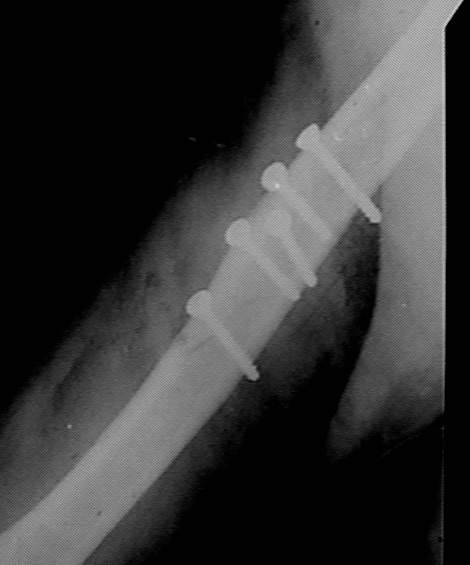

Больная 45 лет оперирована в июле 2002 г, иммобилизация в течение 3 месяцев. После операции были явления неврита лучевого нерва, которые в последующем исчезли. Во время проведения ЛФК отмечается появление болей, патологическая подвижность в месте перелома, деформация плеча.

Считаю неграмотным вкручивание винтов с конусными или закругленными головками, так как они вклиниваясь в кость, раскалывают ее. Два крайних винта на представленных снимках захватили только по одному из отломков. О